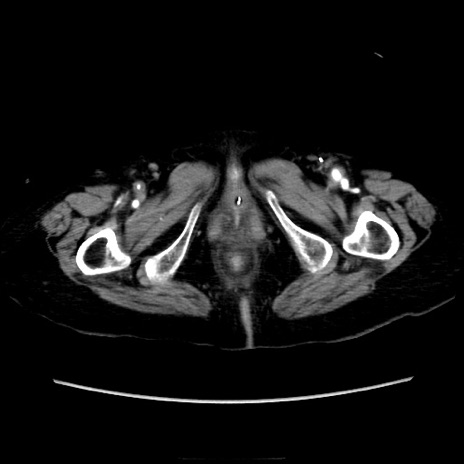

症例40(横断像)

【症例】90歳代女性

【主訴】腹痛・嘔吐

【現病歴】 食欲低下、嘔吐があり昨日他院受診。肺炎と診断され入院となる。入院後より腹部全体に圧痛あり。胃管留置され経過みていたが、症状持続するため、

当院転院となる。

【既往歴】胸椎圧迫骨折、胆石症

【身体所見】腹部:中央に激痛あり、圧痛あり、反跳痛不明

【データ】WBC 17100、CRP 18.82

横断像